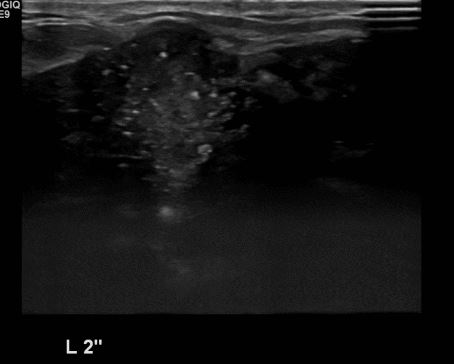

상기환자 좌측 유방에 만져지는 멍울로 내원하신 30대 여성분으로 좌측 2시 방햐에

만져지는 멍울 조직검사 시행하여 좌측 침윤성 유관암 진단 되었습니다.